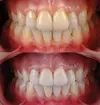

Zirconium Applications

Porcelain Applications

Laminate Veneer